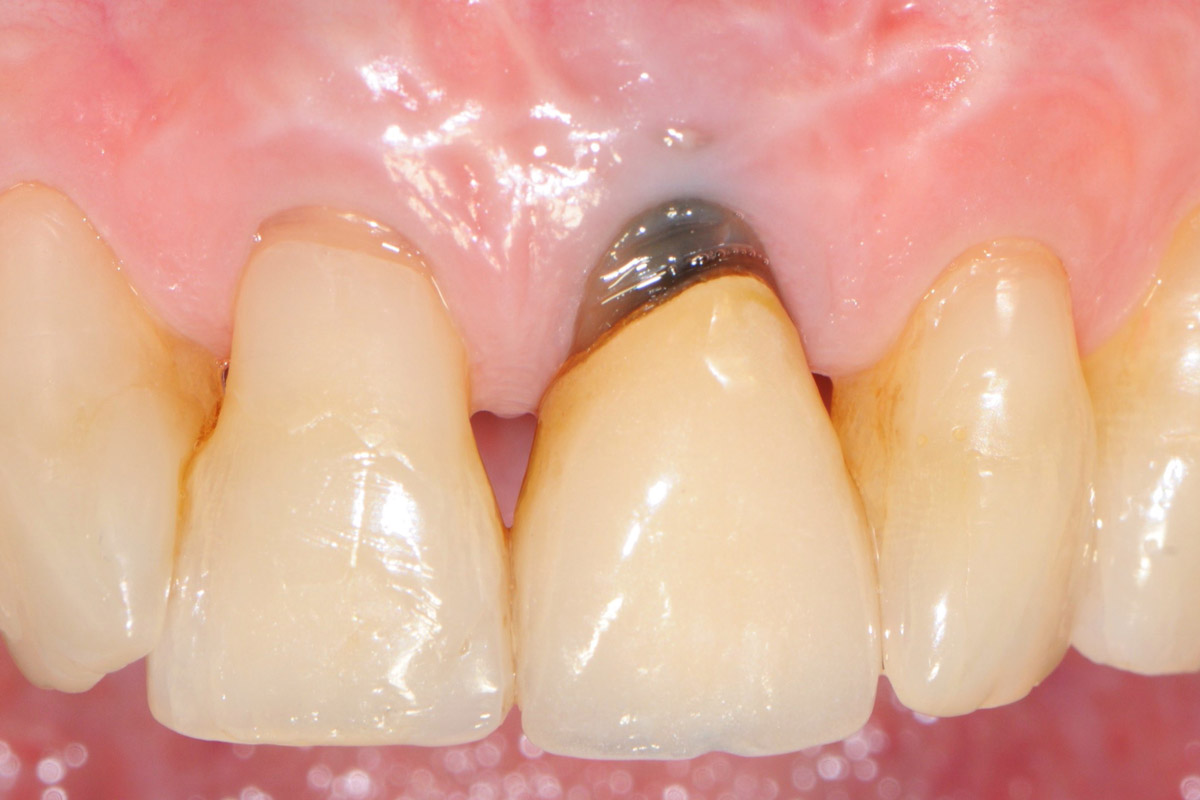

16/18 - Implant placementTooth extraction and socket sealing with mucoderm® - Dr. A. Rossi